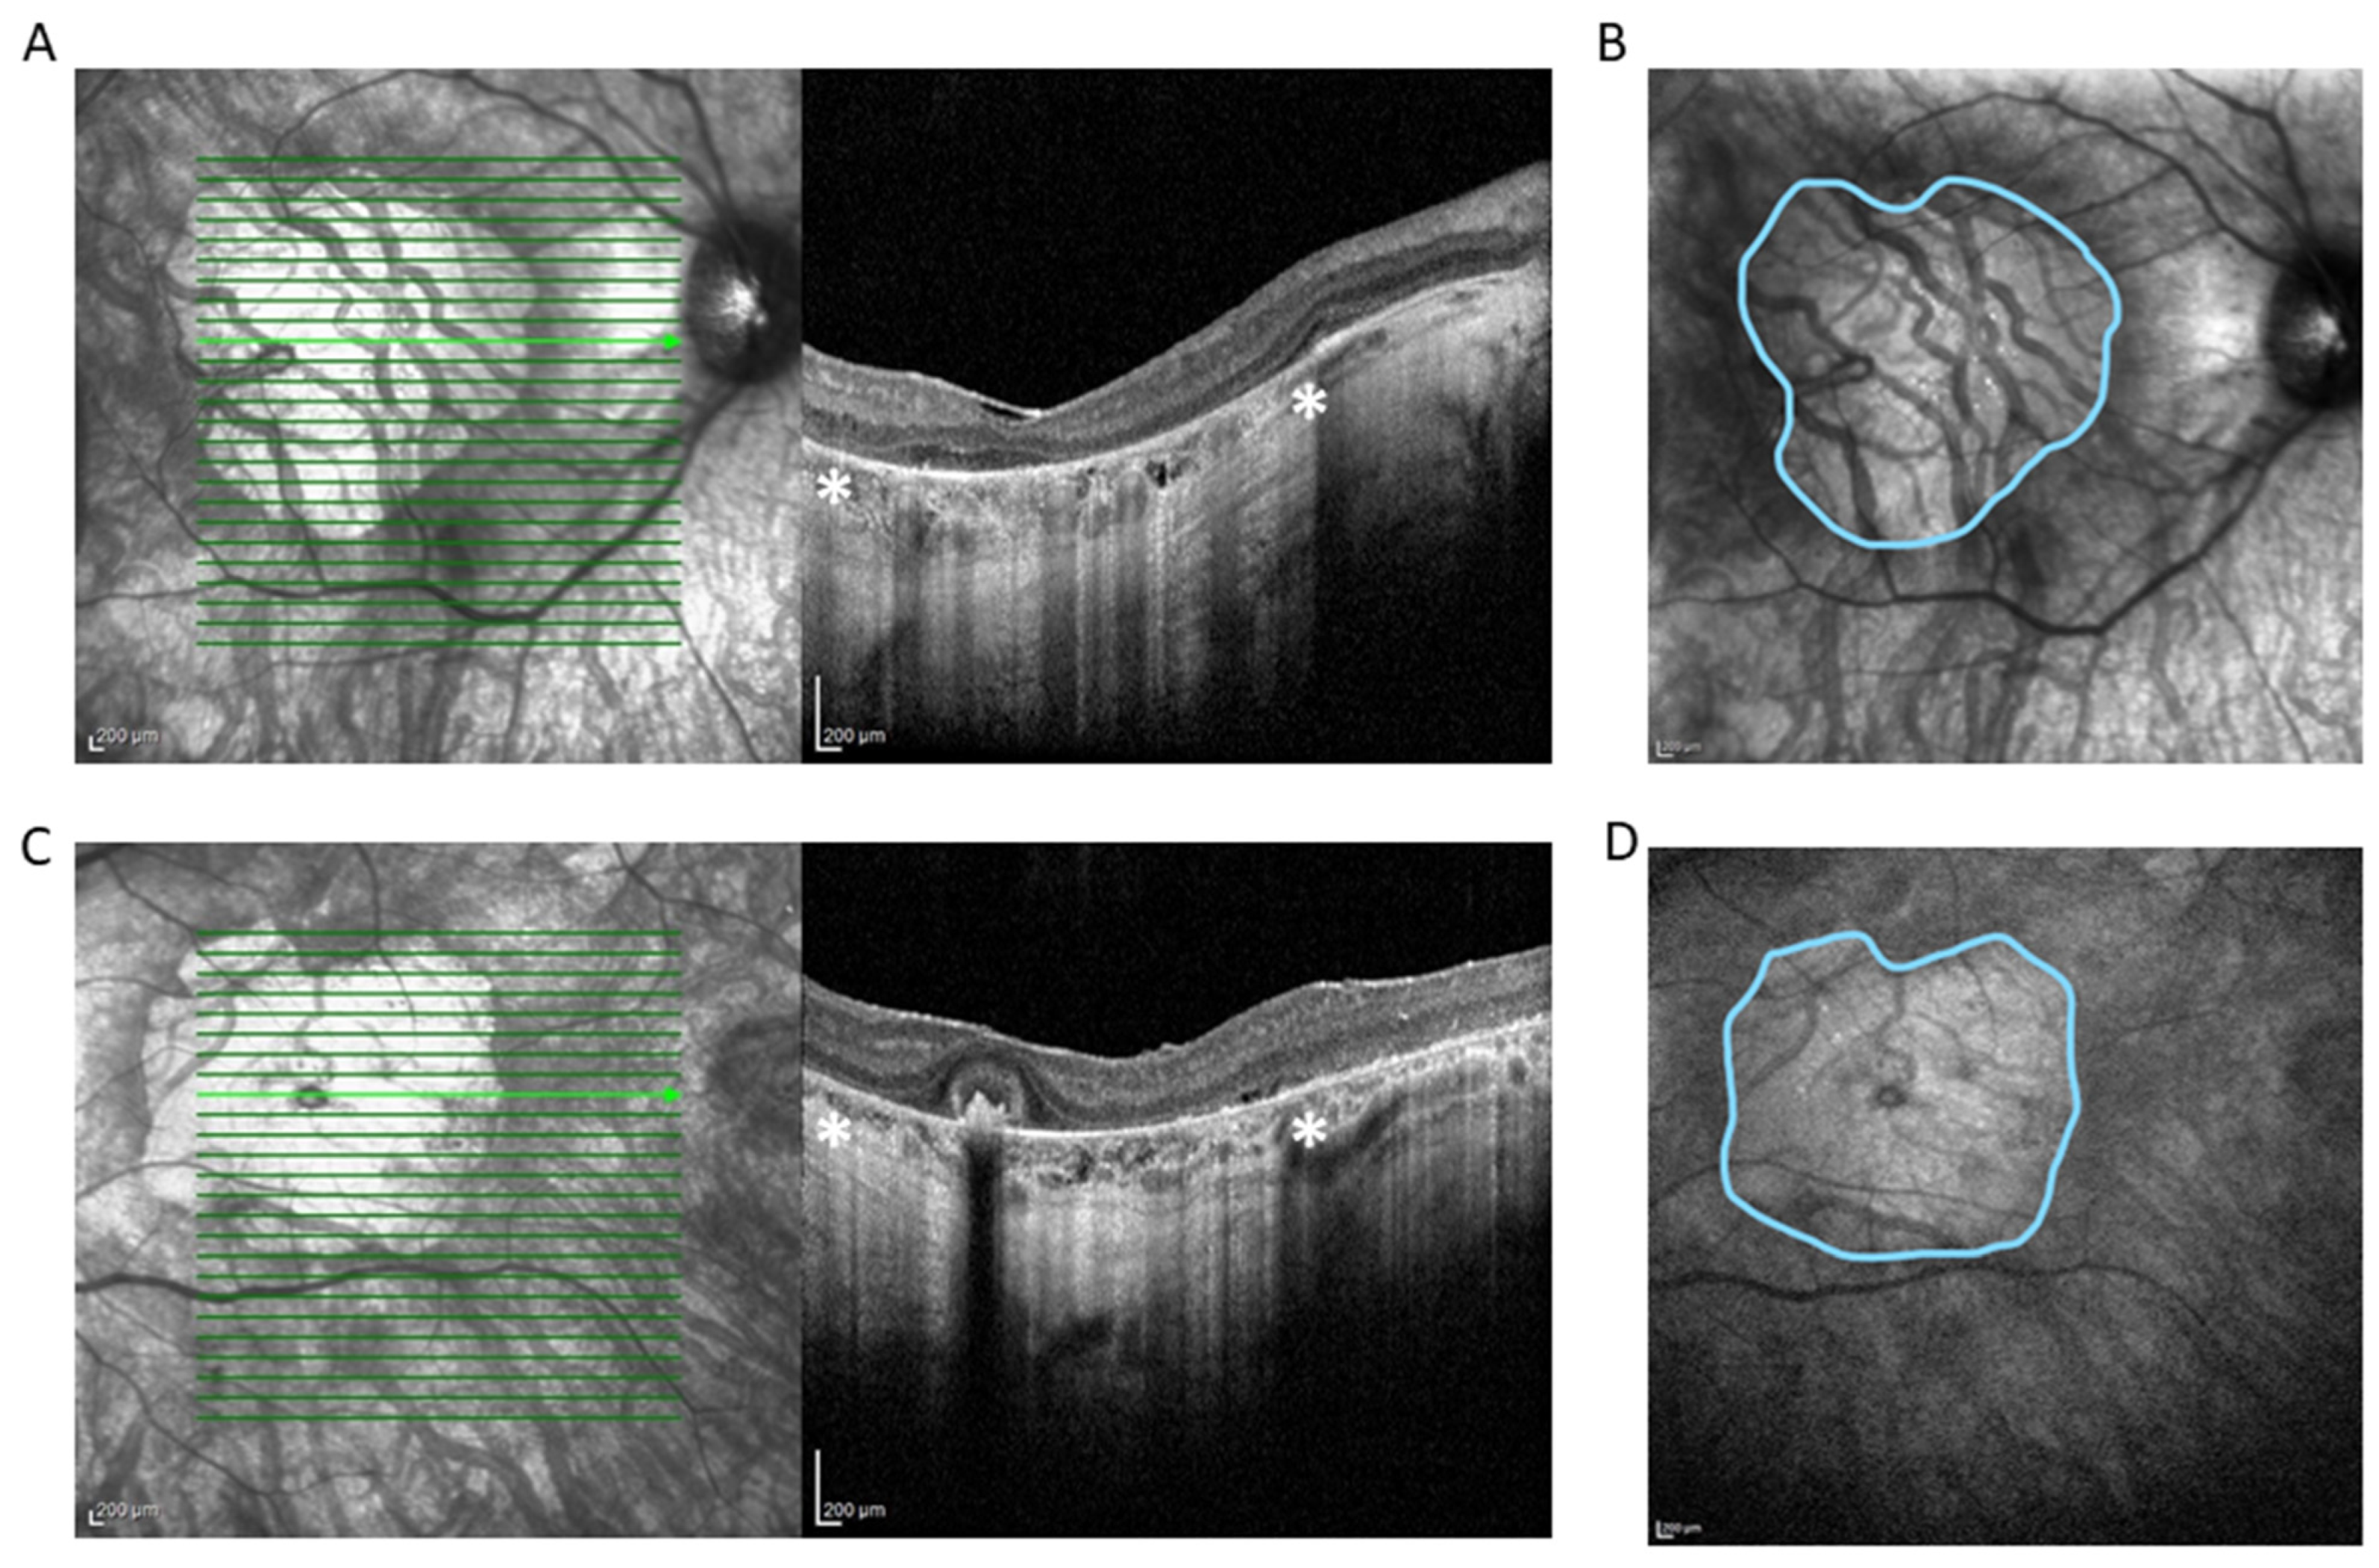

2. Case Presentation